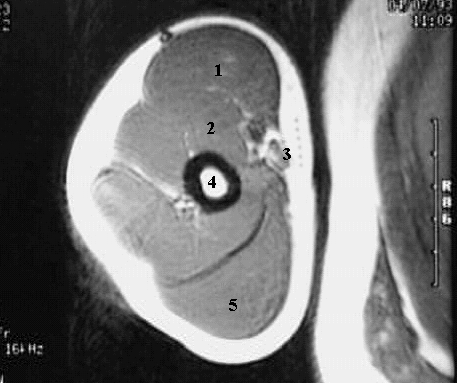

Upper Limbs: Arm MRI Zoom:

1. Biceps Brachii Muscle

2. Brachialis Muscle

3. Brachial Artery

4. Humerus

5. Triceps Muscle.